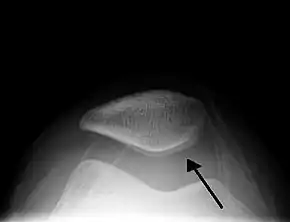

A traumatic right knee effusion. Note the swelling lateral to the kneecap as marked by the arrow. | |